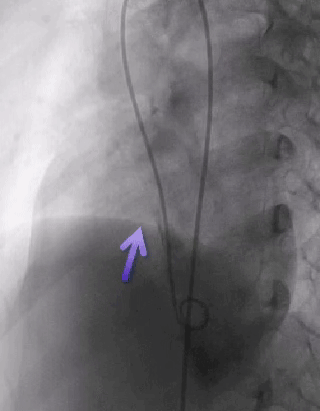

术后复查

术后复查胸片

术后复查心电图,无房室传导阻滞

术后一个月复查

术后随访:

术后随诊1个月

无头痛

无残余分流

无并发症

心脏彩超:心脏超声下可见两个封堵器双盘稳固夹持,无残余分流;

术后1个月心脏超声,房室水平皆无残余分流